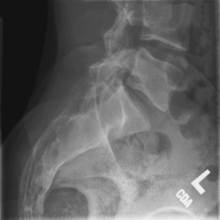

Lateral and lateral L5-S1 critique

• Recumbent in true lateral position, flex hips and knees, align and center midaxillary plane to centerline

• Place support under waist as needed to place entire spine parallel to tabletop (see Note). Provide support between knees.